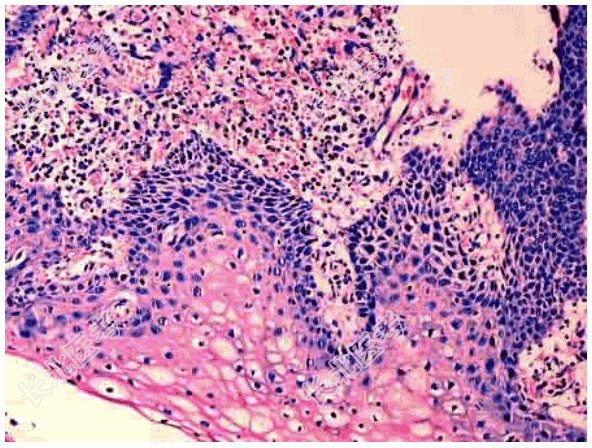

- [材料题] 患者女性,34岁,阴道分泌物增多并有异味,检查宫颈肥大,质硬,宫颈黏膜中度-重度糜烂,取宫颈黏膜活检,显微镜下如图。临床诊断为慢性宫颈炎。

- 简答题1、该疾病的病因包括?

- 简答题2、该疾病的病理改变表现为?